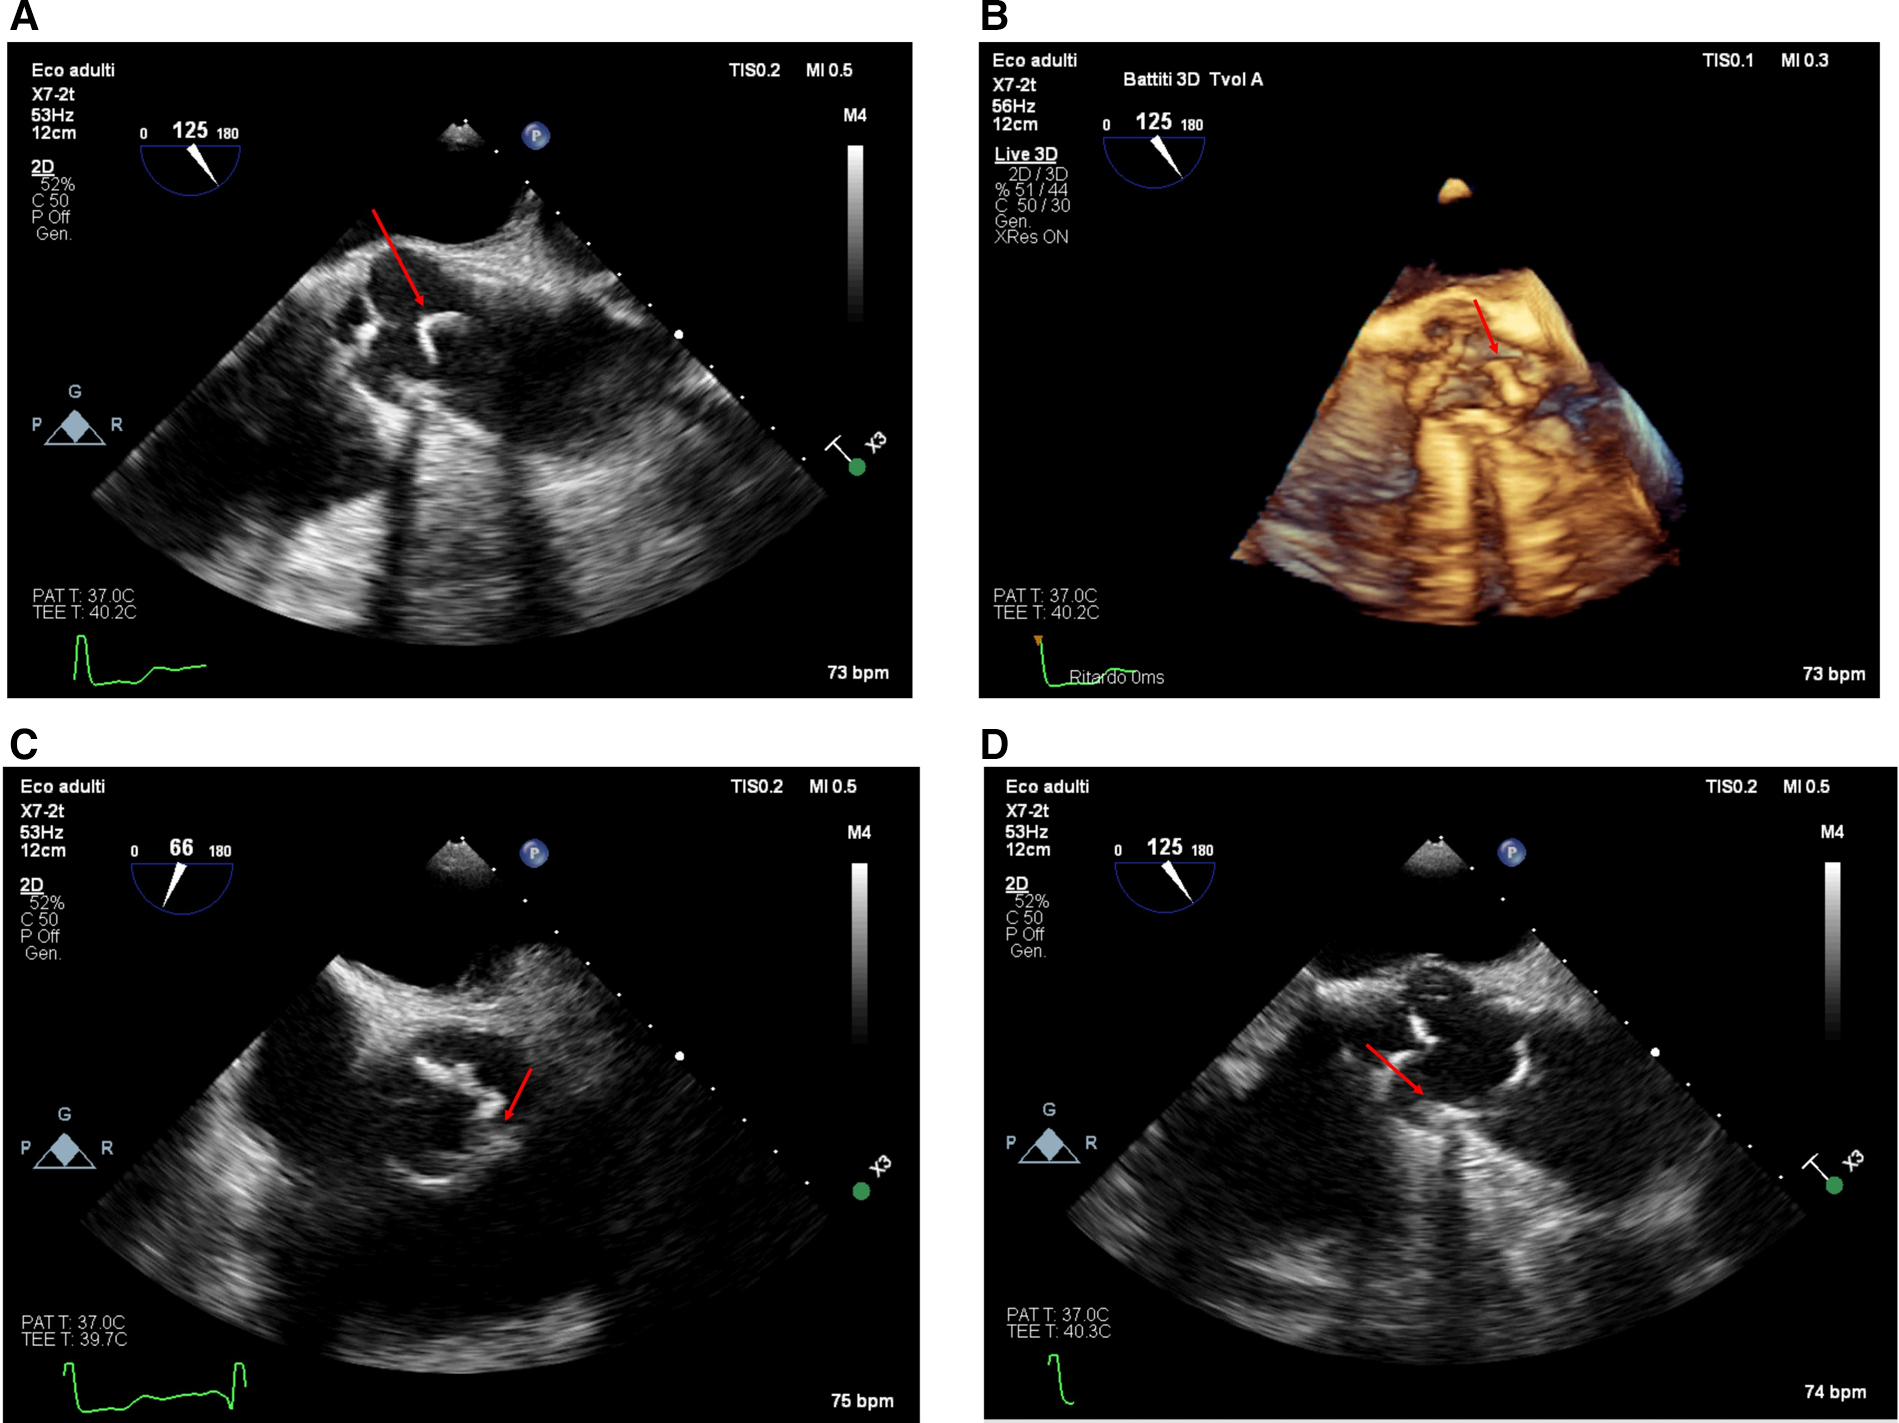

A 3D-TEE was performed to better characterize the lesion (Philips Epiq CVx3D equipped with an X7-2t transesophageal probe). This confirmed a highly mobile, filamentous mass (5 mm × 38 mm) originating from the aortic wall at the level of the sino-tubular junction, attached to a fibrocalcific plaque (Figures 2; Supplementary Video S2). The mass moved with systolic-diastolic excursions without producing obstruction at the valvular level (Supplementary Videos S3–S5). Supplementary Video S6 shows the color X-plane appearance of the lesion in real-time motion.

Figure 2

The appearance of the mass from the transesophageal approach at the mid-esophageal 120-degree view (ME AV LAX view) in 2D [(A), upper left panel, taken from Supplementary Video S2] and with a real-time 3D reconstruction [(B), upper right panel, Supplementary Video S3–S4]. The lesion appeared from the transesophageal approach in the mid-esophageal short-axis view at 66° [(C), lower left panel] and the 125° long-axis view [(D), lower right panel]. The calcified base of the plaque is visible (red arrow); notice the shadow cone [(D), lower right panel—red star] arising from the calcified plaque in the long-axis view.